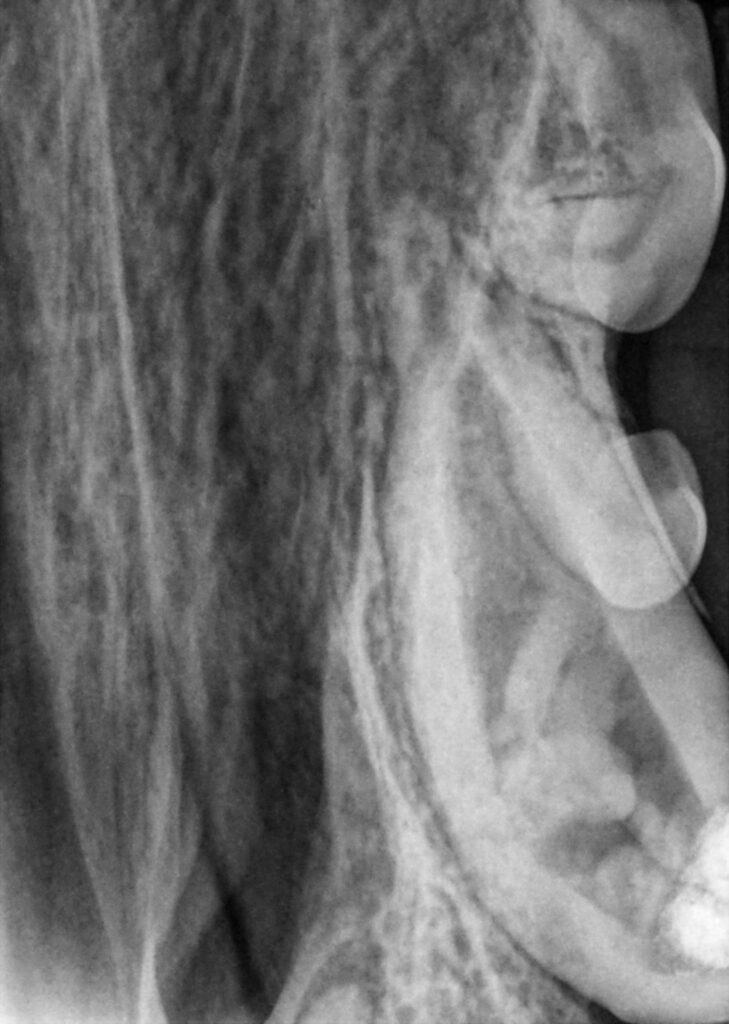

A 6.5-month-old standard poodle was presented to VDS for a fracture of the maxillary left canine (204). (Figures 1a-1c)

Normally, fractured teeth can have a very good prognosis; however, two issues complicated the procedure in this case. First, there was a deep subgingival fracture on the tooth. This extended below the bone, which will create periodontal issues. In addition, because the patient was so young, the root was not complete (Figure 2), and thus standard root canal therapy was not an option.